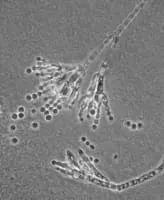

Penicillium chrysogenum photograph

Penicillium chrysogenum or P. notatum is a species of fungus in the genus Penicillium. It is common in temperate and subtropical regions and can be found on salted food products, but it is mostly found in indoor environments, especially in damp or water-damaged buildings.